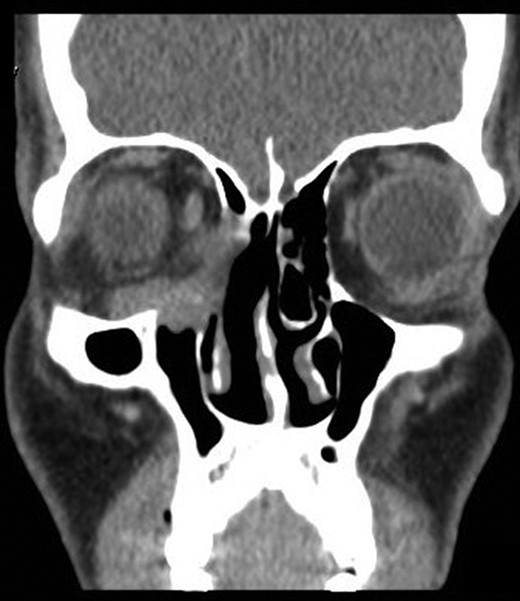

On radiological evaluation, CT scan with contrast of the paranasal sinuses (PNS) revealed a mass involving the right ethmoid sinus with medial wall and orbital floor extension (Fig. 2). The subsequent magnetic resonance imaging (MRI) revealed an infiltrative soft tissue mass occupying the right ethmoid sinus, eroding inferio-medial orbital wall and extending to the extracoanal space (Fig. 3). Positron emission tomography (PET) scan demonstrated an ill-defined 4.5 × 4.2 cm2 mass lesion in the right nasal cavity and ethmoid sinus extending to the right medial orbital floor (Fig. 4). The scan did not reveal any associated lymphadenopathies.

Contrast enhanced computed tomography scan. Coronal CT scan with contrast of PNS showing an enhancing soft tissue lesion in the right ethmoid, eroding the medial and inferior orbital walls.